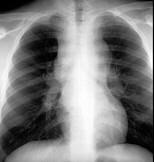

问题 21岁,男,1个月前触及颈部淋巴结肿大,现有上腔静脉综合征,请结合胸片和CT,选出最可能的诊断 ( )

选项 A.结节病 B.淋巴结核 C.转移性淋巴结肿大 D.淋巴瘤 E.胸腺瘤

答案 D